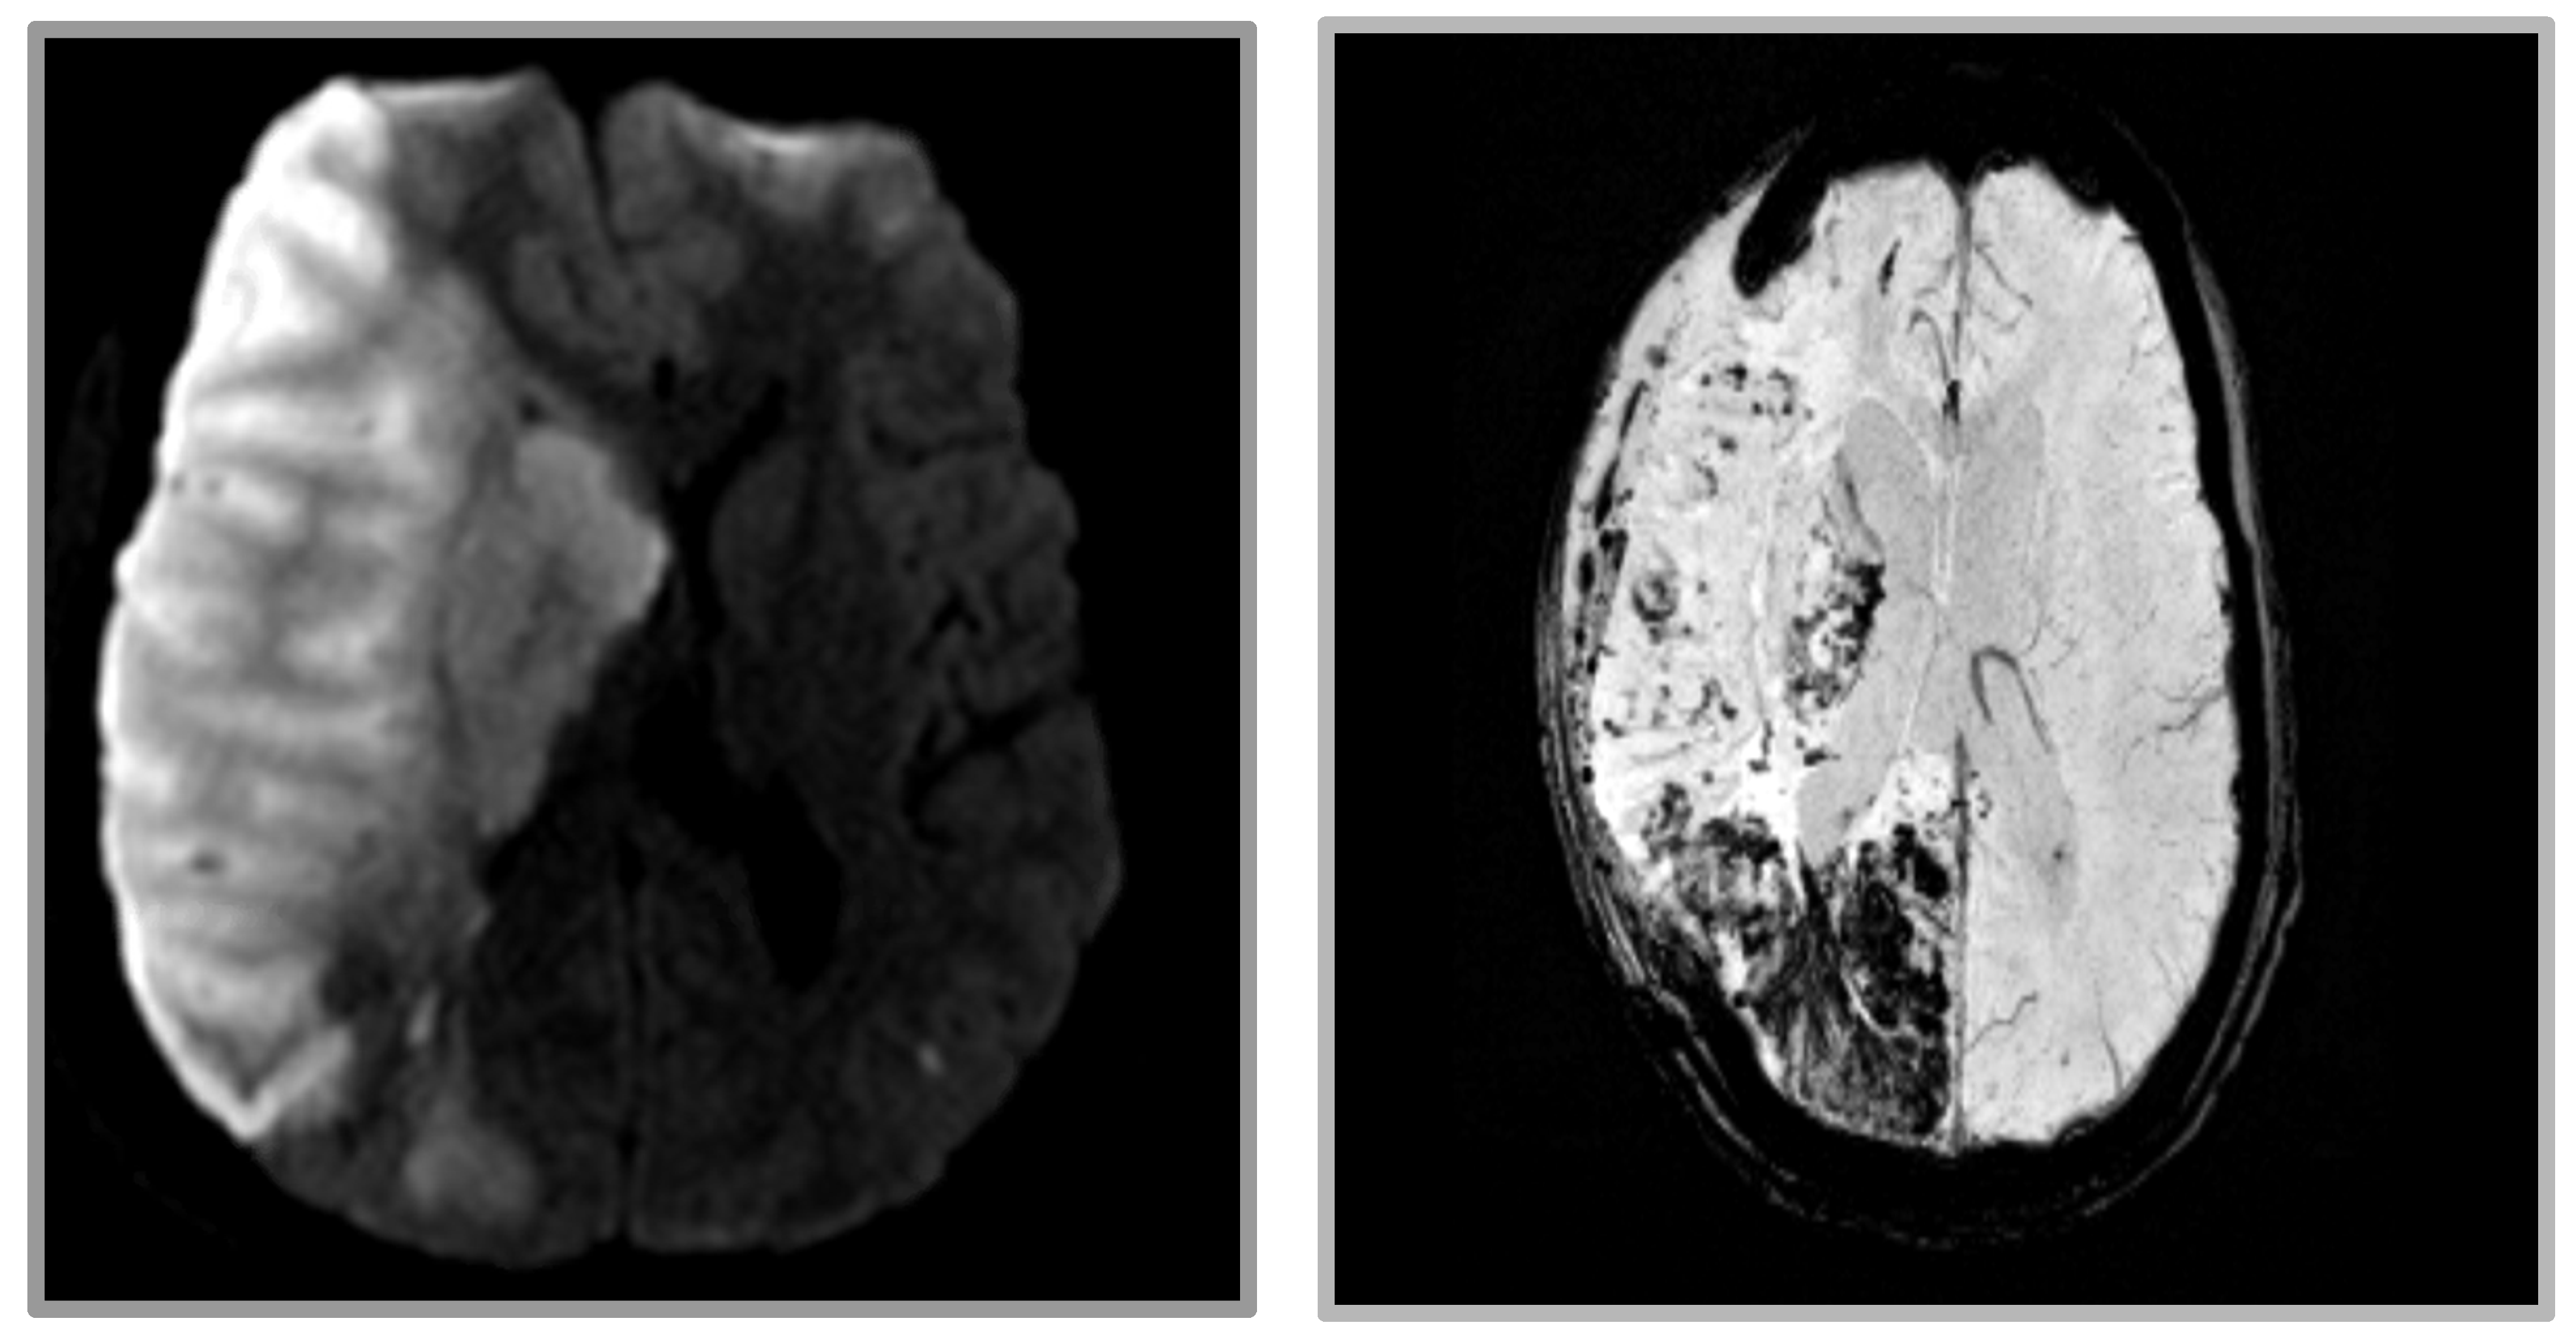

Repeat imaging showed evidence of new microhemorrhages, thus delaying the planned continuation of warfarin therapy (Figure 4). Ten days after returning to rehabilitation, the patient developed gaze restriction and was found to have a new medial right thalamus infarction. Repeat CTAs showed persistent thrombi within the proximal right subclavian and right vertebral artery ostium. As the thrombosis was thought to be the source of the embolus, a decision was made to restart anticoagulation therapy. One month after restarting anticoagulation, imaging showed a resolution of the right subclavian artery thrombus. The patient was then transitioned to chronic dual antiplatelet therapy for secondary prevention.

Figure 4. MRI revealing extensive infarct in the right frontal, parietal, occipital, and deep nuclei. (Left) DWI imaging. (Right) GRE imaging revealing extensive hemorrhagic conversion.